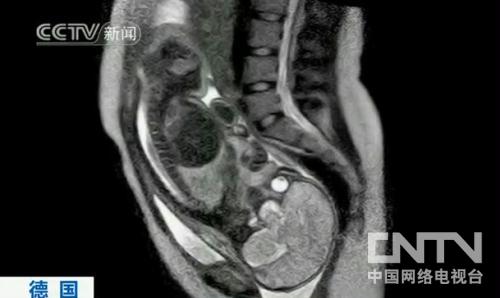

ÖйúÍøÂçµçÊǪ́ÏûÏ¢£ºµÂ¹ú°ØÁÖɳÀïÌØÒ½ÔºµÄÒ½ÉúʵÏÖÁËÒ»ÏîÒ½Ñ§Í»ÆÆ£¬ËûÃÇʹÓú˴ʲÕñ³ÉÏñɨÃèÒÇ»ñµÃÓ¤¶ù³öÉú¹ý³ÌµÄͼÏñ£¬ÕâÔÚÀúÊ·ÉÏ»¹ÊǵÚÒ»´Î¡£ÕâЩͼÏñÊÇÒ»ÃûµÂ¹úÔи¾Í¬ÒâÔں˴ʲÕñ³ÉÏñɨÃèÒÇÄÚÉú²úºóÅÄÉãµÄ£¬Äܹ»°ïÖúÒ½Éú½øÒ»²½Á˽âÉú²ú¹ý³Ì£¬Í¬Ê±Ò²¿ÉÓÃÓÚÕü¾ÈδÀ´µÄÉúÃü¡£